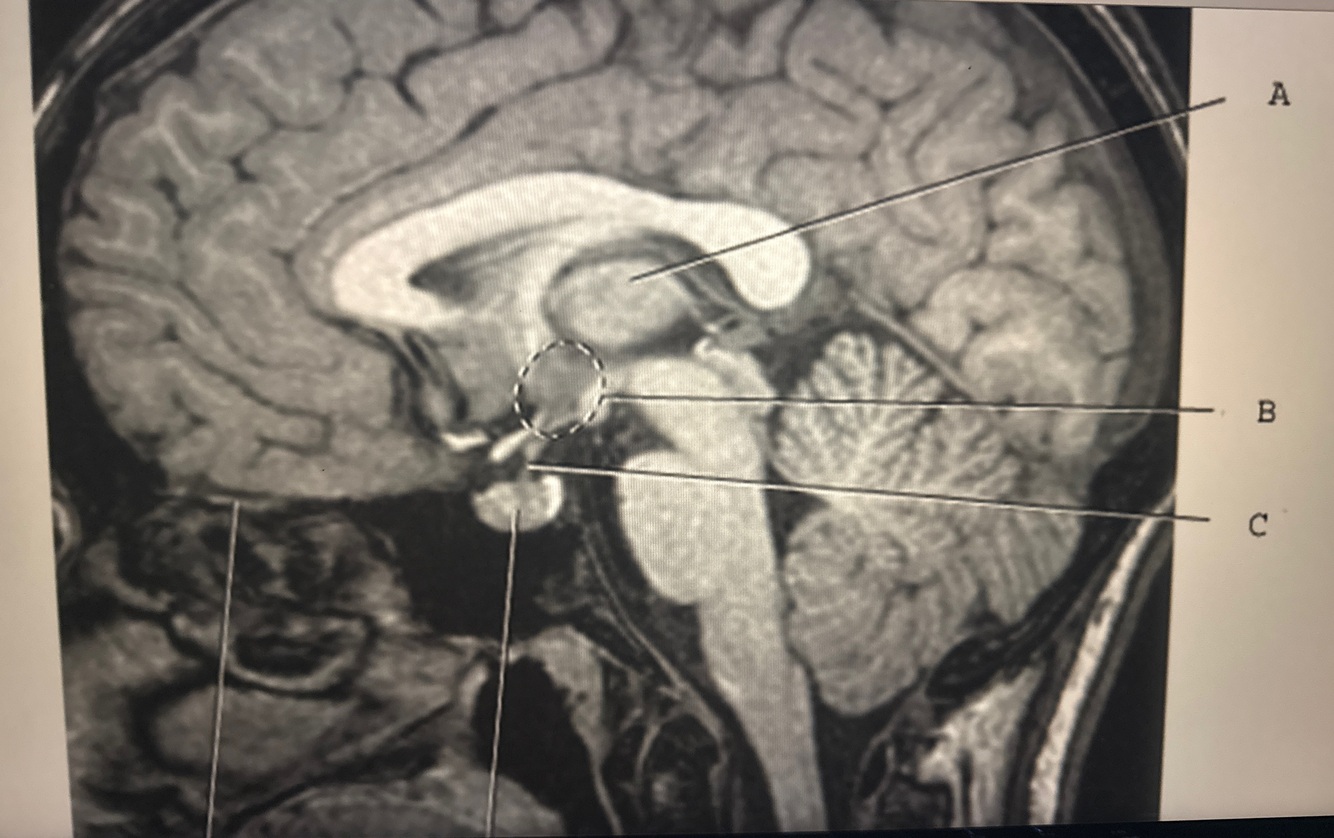

12

Q

Identify B

A. Thalamus

B. Mammillary bodies

C. Hypothalamus

D. Pituitary gland

A